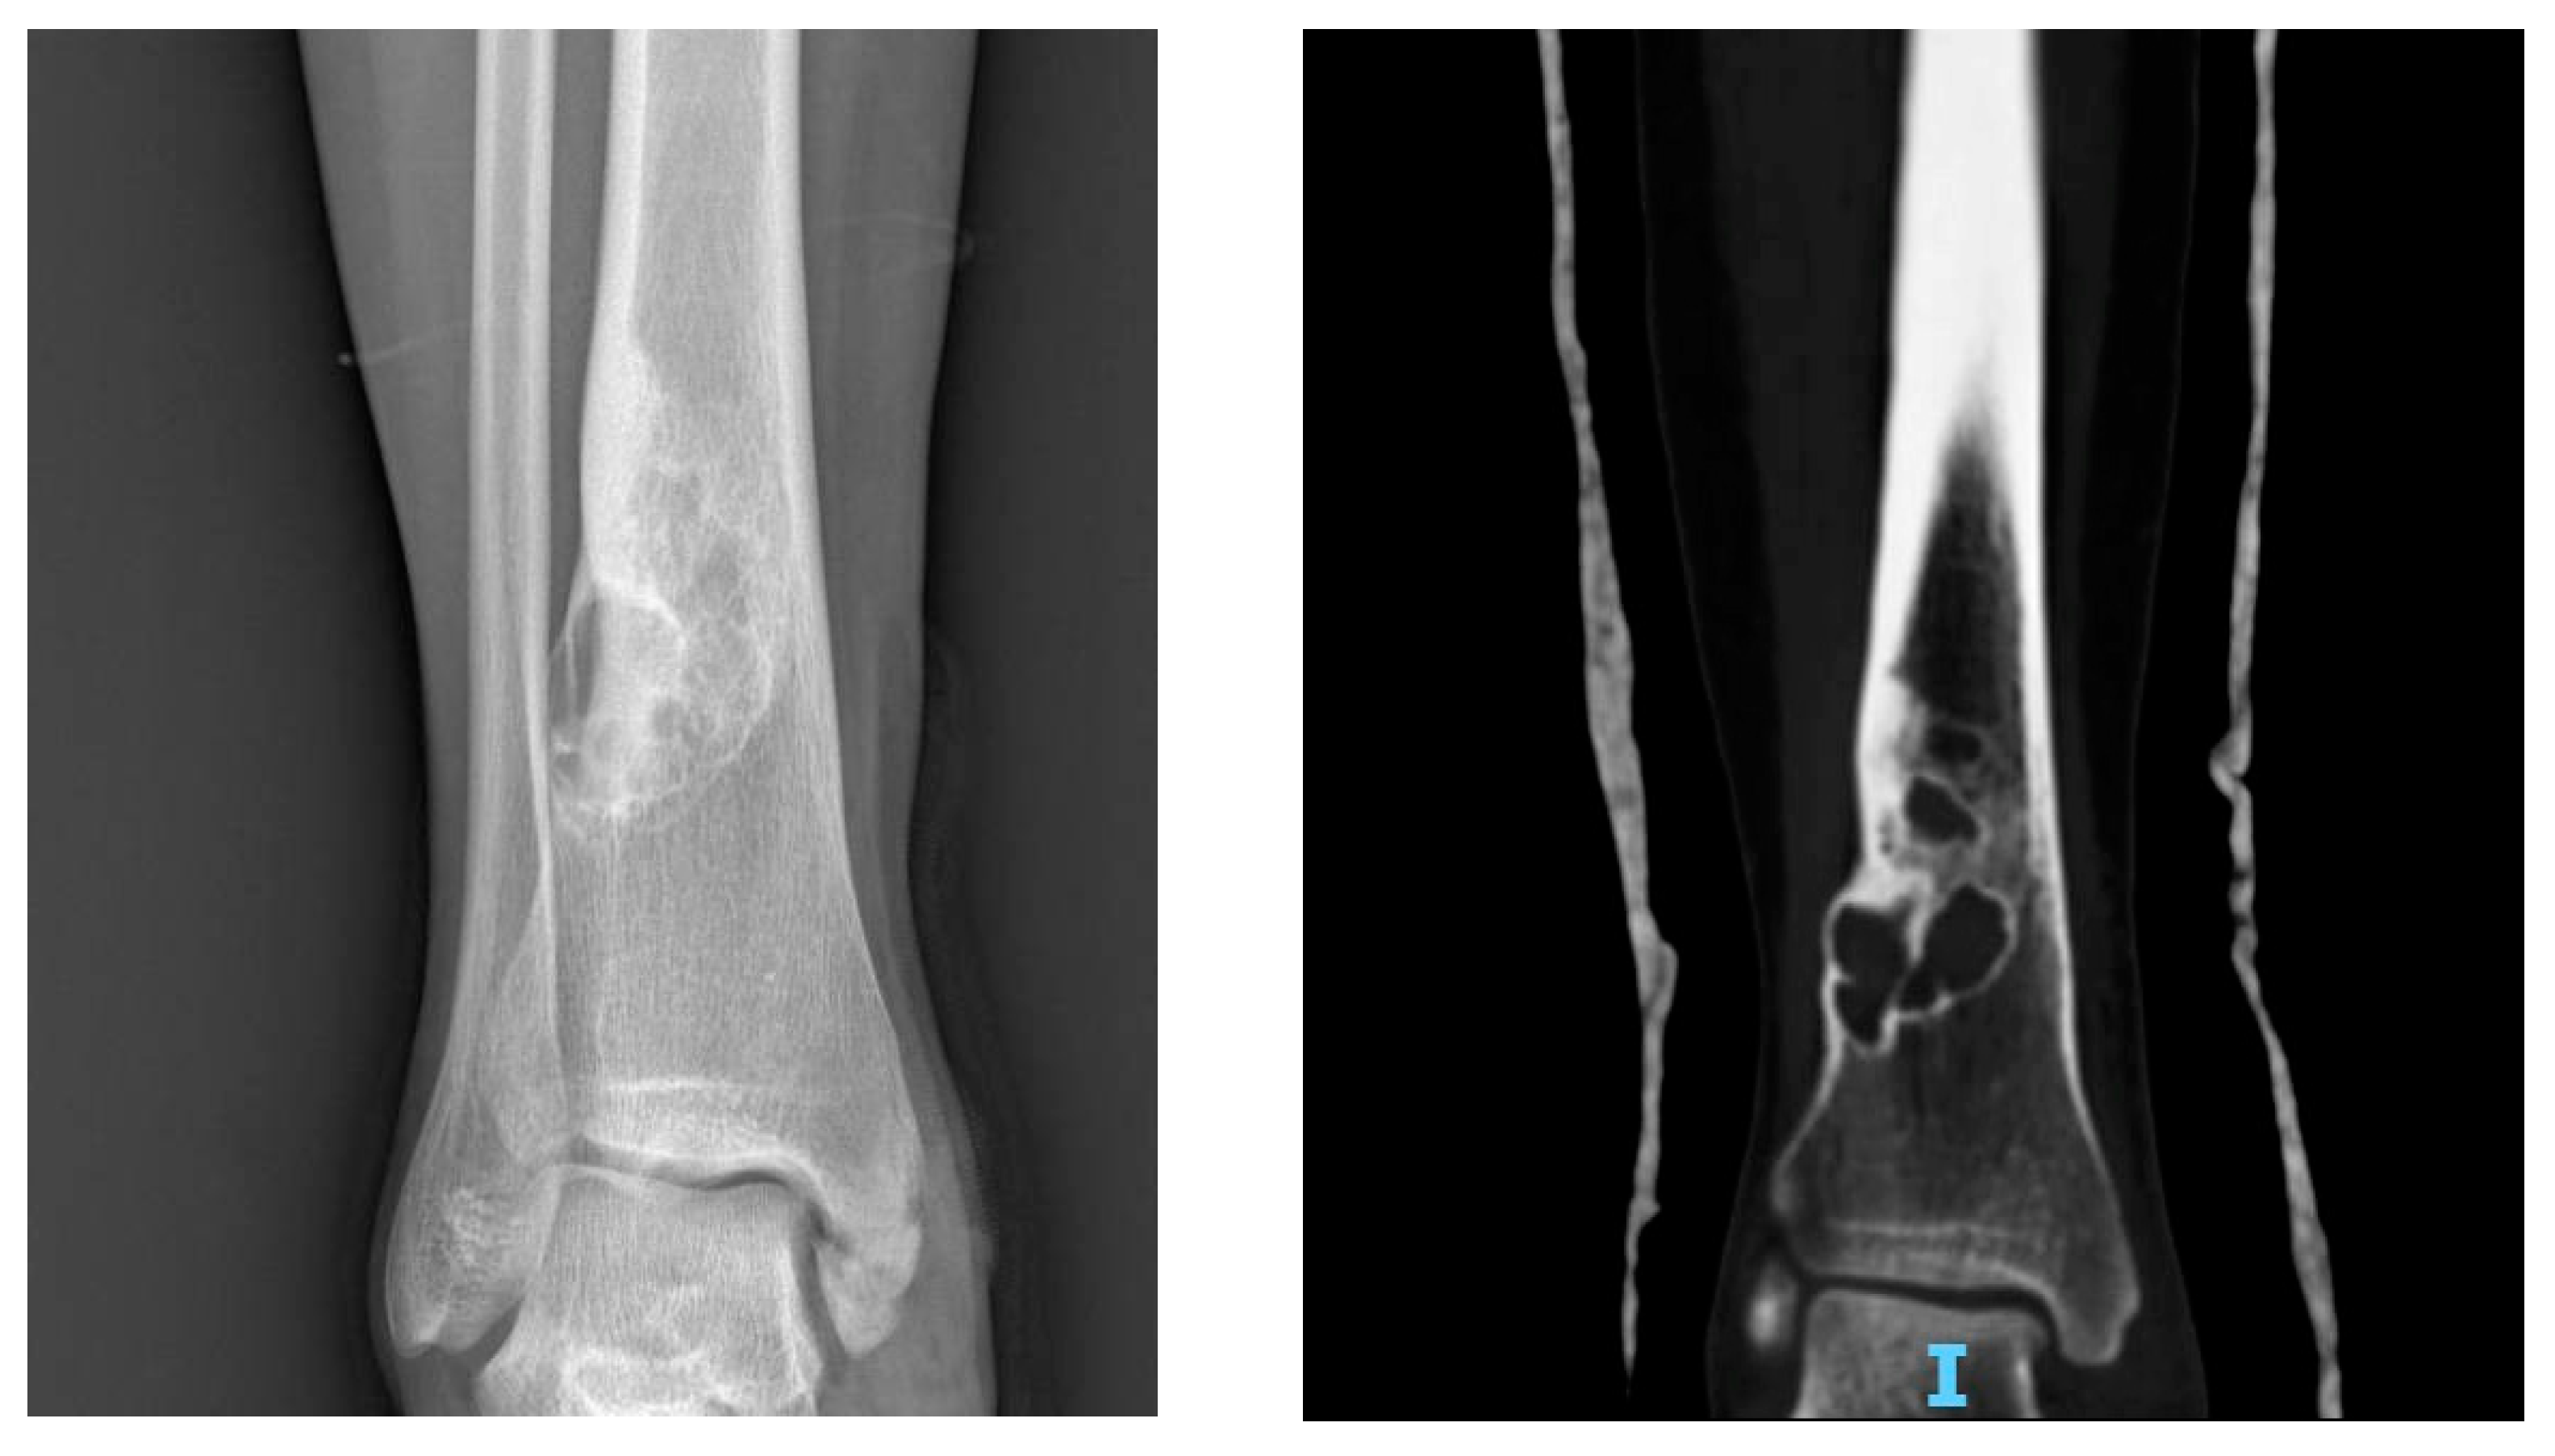

Figure 4. X-rays and CT scan of an NOF, incidentally discovered in a female patient in her 20s.

4.2.5. Imaging

On radiographs, NOFs appear as solitary, eccentric and lytic lesions in the metaphysis of long bones, often polycyclic in shape. Typically, the lesion is lucent, and margins can appear densely sclerotic or indistinct, as well as the cortex, which may be thinned or, in some cases, thickened. When multiple, the most significant length of the lesion is oriented on the long axis of the bone [101]. NOF can spread, causing a thinning of the diaphyseal cortical bone with interspersed sclerosis and anterior or anterolateral bowing (Figure 4).